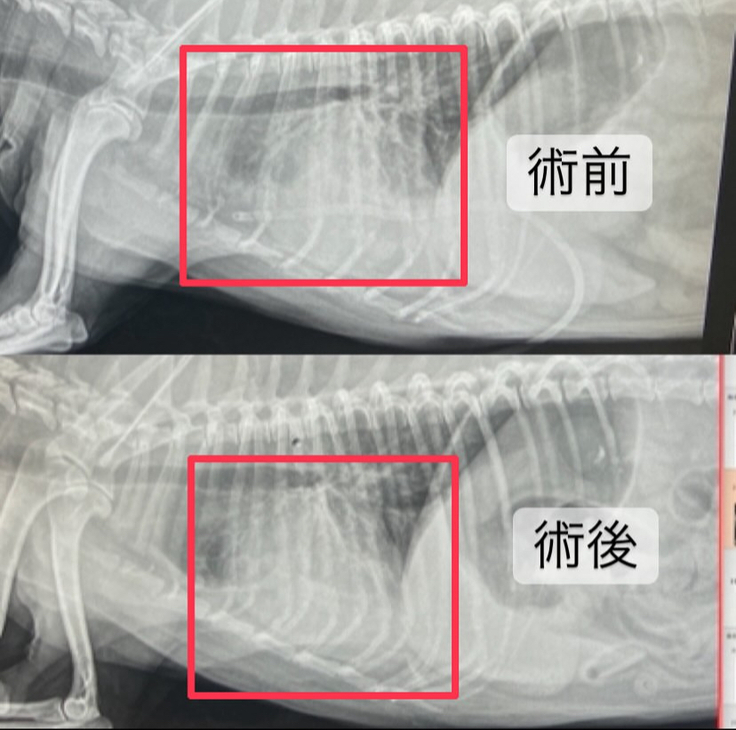

術後3日目

術後3日目となりました🐶❤️🩹

心臓の画像は術前に比べて心臓が小さくなっていて、白くなってしまっていたところも少し減っていました😭✨